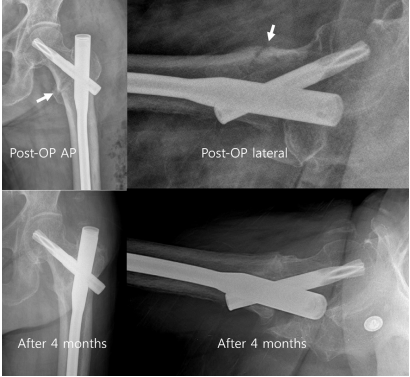

描述一种股骨粗隆间骨折类型,其特点是近端骨块嵌插、前侧皮质不连续以及在轴位侧位片上存在后向塌陷(图1)。

图 1. 骨模型和X光片上前后位和侧位视图上展示的后方塌陷骨折类型。前后位视图上复位似乎是解剖的,但在侧位视图上可以看到复位不良。

图 6. 术后即刻前后位和侧位视图中内侧皮质移位<1个皮质厚度且前侧皮质无移位(箭头所示),以及术后4个月解剖愈合。